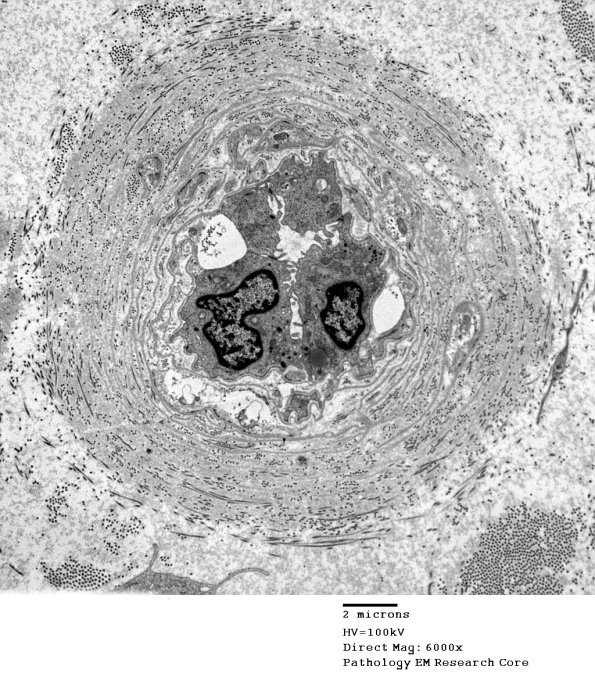

Case 8 History ---- The patient is a 79 year old woman with unspecified hereditary and idiopathic peripheral neuropathy, amyloid and vasculitis. Operative procedure: Right sural nerve biopsy. ---- 8A1,2 The endoneurial vasculature is markedly thickened by alternating circumferential basement membranes and collagen, a pattern most commonly associated with diabetic neuropathy. (electron micrographs)